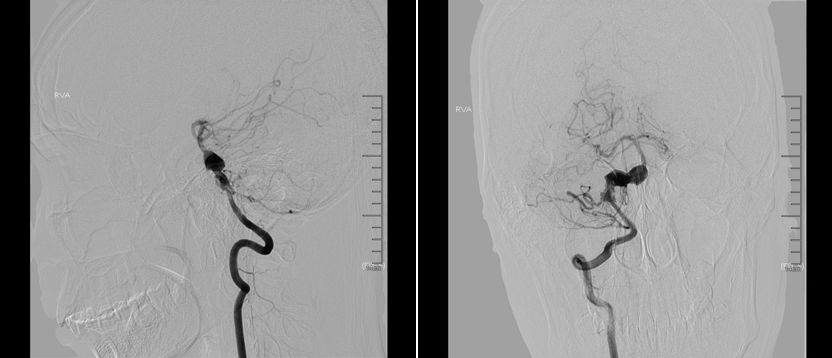

术中路途显示下Synchro-14 200微导丝携Mrksman微导管小心通过PED支架及基底动脉夹层动脉瘤,超选进入右侧大脑后动脉P2段。

PED支架顺利释放,与原支架顺利桥接重叠。术后即刻造影显示PED位置满意,动脉瘤内可见造影剂滞留。

DynaCT显示两枚支架形态良好。